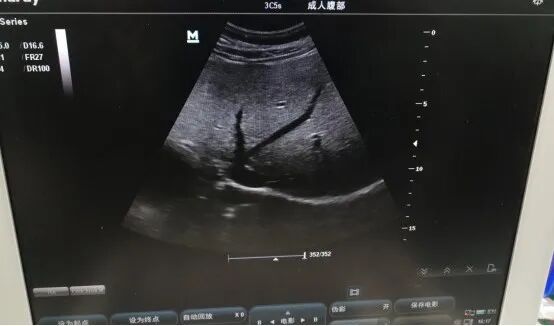

迈瑞3C5S超声故障维修

1. 故障现象

:图像显示异常

2. 故障检测:

(1)观察外部损坏情况。电缆线,尾套完整无明显破损。

(2)经仪器检测发现,声透镜起泡脱胶,正常电容650pf,声头两个阵元偏弱,建议更换。

3.故障判定与分析

:

长期使用导致声透镜起泡脱胶,检测发现声头阵元偏弱,图像显示异常。

故障处理:中修,维修声透镜,更换声头。上机后图像正常。

4.维修后效果: